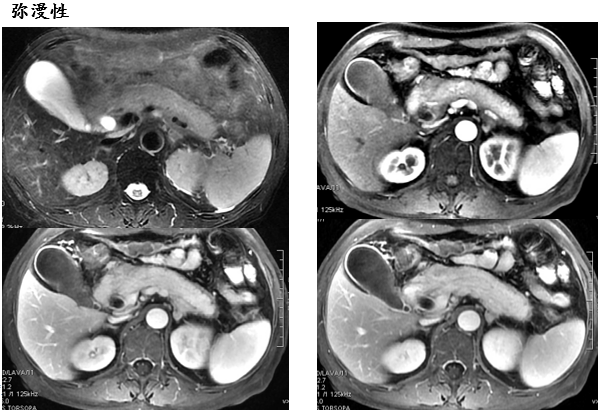

弥漫性

男,58 岁,腹痛黄疸、胆肠引流术后四年,反复黑便十天